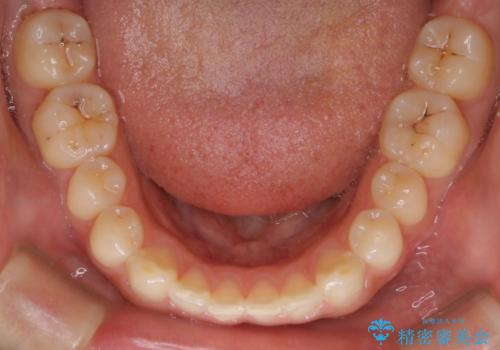

再矯正ということでがたつきはなくきれいに並んでいましたが、上下のアーチ(歯列弓)の大きさのバランスが悪く、結果的に後戻りの原因になってしまっていました。今回は下のアーチを小さくするためにIPRを行い、かみ合わせのバランスを治しながら前歯の隙間を閉じました。